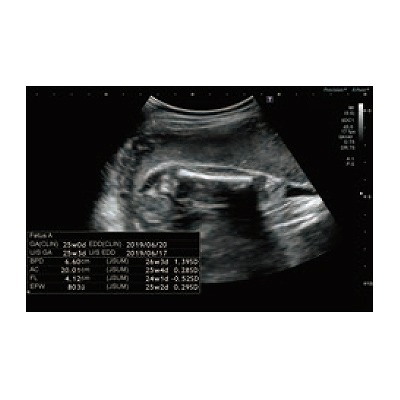

●心機能計測、胎児計測もサポート